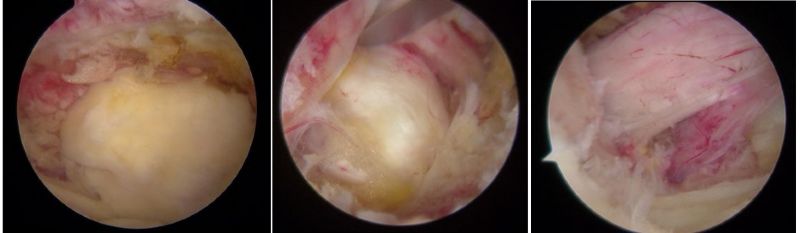

骨科內鏡下的腰椎組織

近年來,隨著脊柱內鏡技術突破性發展,以"精準減壓、最小侵襲"為核心理念的微創術式已成為60%以上腰椎手術患者的優先選擇,特別是合并多種疾病、無法耐受開放手術的高齡患者。相較于傳統開放式手術需大面積剝離肌肉組織、損傷脊柱穩定性的弊端,該技術通過直徑僅7-8毫米的骨科內鏡工作通道,在局部麻醉下借助高清內鏡可視化系統精準定位病灶,實現了"靶點精準治療"的突破性進展。

UBE是unlateral、biportal、endoscopic三個英文單詞的首字母,也就是“單側雙通道脊柱內鏡”。臨床上簡稱為:“UBE”。其技術的核心是雙通道:一個是內鏡通道,另一個是器械操作通道,兩處皮膚切口各僅約0.8cm。與傳統開放手術相比,它借助天然解剖間隙建立微創工作通道,解除神經壓迫。對椎旁肌肉損傷較小,且能夠最大程度地保留完整的脊柱結構,維持了術后脊柱的穩定,具有創傷小、出血少、恢復良好、并發癥少、費用低等優點,大幅提升了手術的效率和安全性。